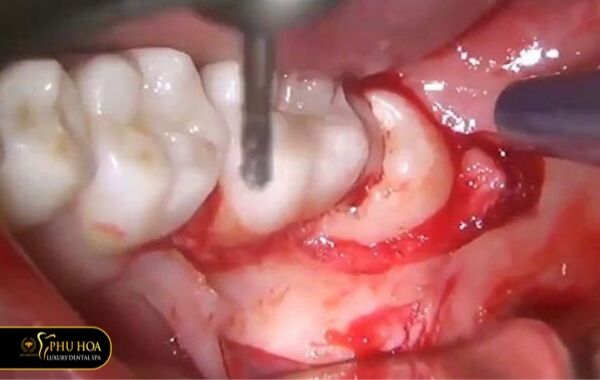

Hiện nay, công nghệ nhổ răng khôn bằng máy siêu âm piezotome giúp loại bỏ răng khôn một cách dễ dàng. Ít đau và nhanh lành.

Đây là loại máy hiện đại và tiên tiến. Nó có mũi siêu âm bén và linh hoạt, chỉ tác động vào những phần mô cứng. Không tác động đến các mô mềm, nhẹ nhàng tách răng khôn ra khỏi hàm.

Sử dụng máy siêu âm piezotome là công nghệ hiện đại. Được nhiều phòng khám ứng dụng trong quá trình điều trị, nhổ răng cho bệnh nhân.